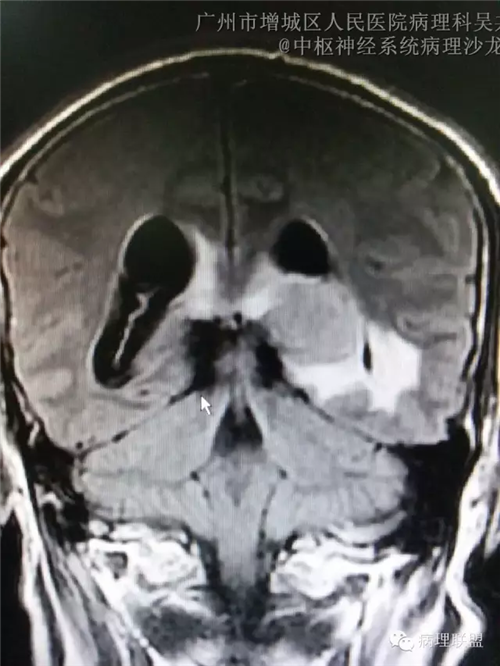

脑部影像学结果: